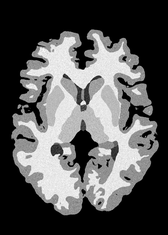

4.2 Registration to a 100 micron ex-vivo brain MRI volume

To showcase the efficacy of our method on real large scale images, we register a 250 in-vivo MRI image (Lüsebrink et al., 2017) to a 100 ex-vivo FLASH human brain volume (Edlow et al., 2019). This represents an inverse problem with more than 11.2B optimizable parameters (compared to 20M for clinical datasets), or 44.8GB of GPU memory. The entire problem does not fit on most GPUs, necessitating distributed multimodal registration. We optimize a composite transform - affine followed by a diffeomorphic mapping; details can be found in Section E.1. Multimodal deformable registration took 58 seconds on 8 NVIDIA A6000 GPUs, which is unprecedented at this resolution. Fig. 6 shows qualitative results, highlighting the ability to register highly detailed structures such as cerebellar white matter; these structures are not visible at macroscopic scales. The resultant advantages of performing registration at this scale can allow researchers to characterize the neuroanatomy at microscopic resolutions and allow morphometric analysis of cortical layers and subcortical nuclei among other structures.